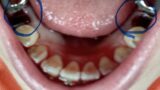

前歯が上がった?

前歯の位置が変わってきました。

上がっている感じです。

隣の歯と比べてびっくりです!